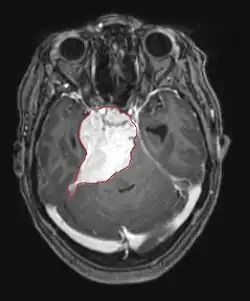

La tomodensitométrie (TDM) et L'imagerie par résonance magnétique (IRM) peuvent détecter efficacement une néoplasie dans le cerveau. L'IRM est plus sensible que la TDM pour identifier les lésions, mais présente des contre- indications pour les patients porteurs de stimulateurs cardiaques, de prothèses incompatibles, de clips métalliques et contre-indications. La TDM reste la méthode de choix pour détecter les calcifications au sein des lésions ou les érosions osseuses de la calotte ou de base du crâne. L'utilisation d' agents de contraste, iodés dans le cas du scanner et paramagnétiques (gadolinium) dans le cas de l'IRM, permet l'acquisition d'informations sur la vascularisation et l'intégrité de la barrière hémato-encéphalique, une meilleure définition de la tumeur tumorale par rapport à l' œdème environnant et à la génération d' hypothèses sur le degré de malignité. L'examen radiologique permet également d'évaluer les effets mécaniques et les modifications importantes des structures cérébrales résultant de la tumeur, telles que l' hydrocéphalie et les hernies, dont les effets peuvent être fatals. Enfin, en préparation à la chirurgie, ce diagnostic peut être utilisé pour déterminer la localisation de la lésion ou l'infiltration de la tumeur dans des zones vitales du cerveau. À cette fin, l'IRM est plus efficace que la tomodensitométrie car elle peut fournir des images en trois dimensions.

Les outils d'imagerie radiologique diagnostique mettent en évidence la modification du tissu néoplasique par rapport au parenchyme cérébral normal (par le biais de modifications de la densité tissulaire imagée électroniquement en TDM et de l'intensité du signal en IRM). Comme la plupart des tissus pathologiques, les tumeurs sont également reconnaissables par une accumulation accrue d'eau intracellulaire. Dans la tomodensitométrie, ils apparaissent hypodenses, c'est-à-dire de moindre densité que le parenchyme cérébral, dans la tomographie par résonance magnétique nucléaire avec relaxation spin-réseau hypointense et en relaxation spin-spin ainsi que l' hypersignal en pondération protonique (PD).

Dans le tissu tumoral, en général, la plus grande proportion d'amélioration du contraste est due à la barrière hémato-tumorale particulière qui permet le passage de l'iode (CT) et du gadolinium (IRM) dans l'espace interstitiel extravasculaire intratumoral. Cela augmente le signal (densité ou intensité) de la tumeur. Cependant, des précautions doivent être prises pour s'assurer que l'amélioration du contraste ne différencie pas définitivement la néoplasie de l'œdème péri-lésionnel. En fait, la découverte anatomo-pathologique dans le tissu tumoral infiltrant malin du gliome, comme dans le glioblastome et l'astrocytome anaplasique, montre également au-delà de l'œdème vasogénique causé par la destruction de la barrière hémato-encéphalique par la tumeur. Cette dernière condition clinique est difficilement détectable par imagerie diagnostique.

La tomodensitométrie du cerveau montre généralement une masse tissulaire qui peut être améliorée par l'un ou l'autre contraste. Au scanner, les gliomes de bas grade apparaissent généralement isodenses au parenchyme normal et peuvent donc ne pas présenter de rehaussement de contraste. De même, les lésions de la fosse crânienne postérieure sont difficiles à identifier au scanner. Par conséquent, les seuls résultats d'une telle tomographie ne sont pas toujours suffisants à des fins diagnostiques. Dans les cas douteux, l'utilisation de l'imagerie par résonance magnétique plus sensible est indispensable.

Sur-L'IRM montre une tumeur intracrânienne comme une lésion massive qui peut devenir plus luminescente après utilisation du produit de contraste. Cependant, il y a toujours une anomalie de signal dans -L'imagerie par résonance magnétique, qui indique la présence d'une néoplasie ou d'un œdème vasogénique. Habituellement, une luminescence accrue (amélioration du contraste) indique une tumeur d'un grade supérieur de malignité. Un anneau de contraste est caractéristique du glioblastome, avec la partie luminescente correspondant à la partie vitale de la tumeur maligne, et la plus foncée - zone hypointense correspondant à une nécrose tissulaire.

Les astrocytomes diffus II apparaissent sur la tomodensitométrie. Grades que les lésions moins intenses. Dans l'imagerie par résonance magnétique préférée, les agents de contraste peuvent ne pas être en mesure de mettre en évidence ces néoplasmes, leur luminescence peut être plus fine et plus faible. Un plus intense peut indiquer des tissus d'anaplasie accrue. Dans la mesure du possible, une biopsie est suggérée pour obtenir des échantillons de la partie anaplasique de la tumeur.